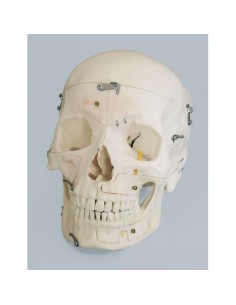

Dal cranio in 22 parti con incastri magnetici ai modelli di colonna vertebrale, da quelli di articolazioni a quelli di cuore, ogni pezzo della nostra collezione è progettato per un’immersione totale nello studio dell’anatomia umana. I nostri modelli, realizzati tramite scansioni di ossa vere, garantiscono un’esperienza tattile autentica e una fedeltà di peso quasi identica agli originali.